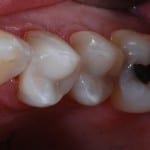

A filling will plug the hole and stop future pain or discomfort. There are a variety of materials, the most common of which are amalgam (silver) and composite (white) although we are increasingly using highly aethetic and strong ceramic fillings made with our CEREC system.  We are the only practice in Harrogate and Knaresborough who are able to offer this technology

Many people opt for white fillings which match the colour of the natural tooth. White fillings are a great way to repair teeth without spoiling their appearance, and can also be used to improve the appearance of badly shaped and  ‘gappy’ teeth.

Larger cavities are best restored using all ceramic fillings made using our unique CEREC system. These give the ideal combination of great aesthetics and strength for long lasting restorations